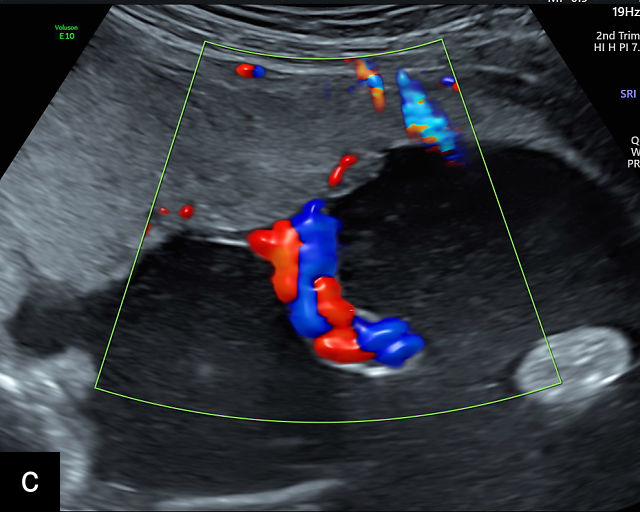

- The umbilical cord insertion (Figure 2b,c) and placental margin (Figure 2d) – Special attention should be paid to the site at which the umbilical cord or vessels insert into the placenta, as well as the marginal regions of the placenta, to identify potential abnormalities.

(a) Transabdominal grayscale ultrasound image of the placenta showing the four key placental regions: the myometrium (gray area), decidua (black line), chorion (light gray thin line), placental body (p), and the chorion–amnion interface. (b) Grayscale ultrasound image of the umbilical cord insertion into the placenta. (c) Same view as in (b) but with color Doppler applied. (d) Normal placental edge (arrow), which is a common location for placental lakes. (e) Rolled placental edges (arrows) in circumvallate placenta (p).

Hernandez-Andrade and colleagues assert that most placental abnormalities can be accurately identified using gray-scale ultrasound alone, but color Doppler can be a valuable tool in distinguishing between certain lesions.2,15 By following this structured approach, these authors propose that the majority of placental and cord abnormalities can be effectively recognized, leading to improved diagnostic accuracy and better prenatal care.2